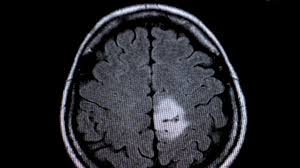

Epileptiforme Anfälle Krampfanfälle Kopfschmerzen äußern sich in Berührungs- oder Licht-Empfindlichkeit. Der Charakter und die Intensität des Schmerzes werden als neu empfunden. Ferner könnte eine steigende Vergesslichkeit Sprachstörungen und Gangstörungen für einen Tumor im Gehirn sprechen. Ein Hirntumor bei Hunden macht sich aber nicht nur durch Wesensveränderungen bemerkbar. Wie äußert sich ein Hirntumor. Ähnliche Symptome können auch bei folgenden Erkrankungen auftreten. Ist zum Beispiel der linke Arm des Betroffenen gelähmt befindet sich der Hirntumor vermutlich in der rechten Hirnhälfte. Auch bei Krampfanfällen kann der Arzt manchmal auf den Ort des Hirntumors schließen. Forscher aus Großbritannien haben 39.

Hierzu zählen zum Beispiel auch epileptiforme Anfälle oder Krampfanfälle. Von den vielen gutartigen benignen und oft heilbaren Tumoren. Das Problematische an Hirntumoren ist dass sie egal ob gut- oder bösartig in einer Körperregion wachsen die sich nicht nach außen ausdehnen kann. Wie äußert sich ein Hirntumor. Auch bei Krampfanfällen kann der Arzt manchmal auf den Ort des Hirntumors schließen. Hierzu zählen zum Beispiel auch epileptiforme Anfälle oder Krampfanfälle. Ein Hirntumor äußert sich oftmals auch durch psychische Veränderungen die auf keine bestimmte Ursache zurückzuführen sind.